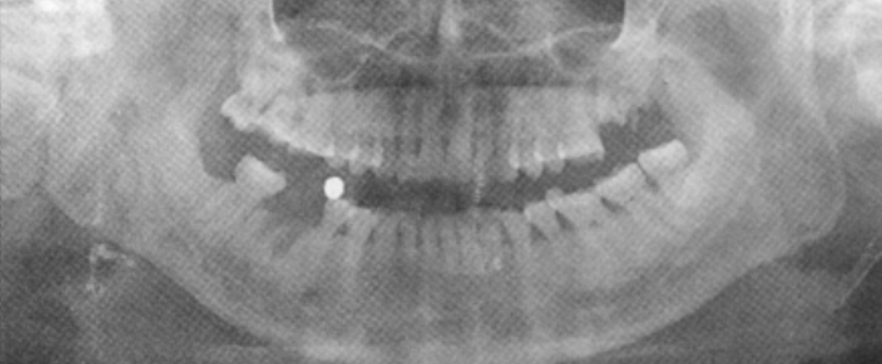

种植牙流程